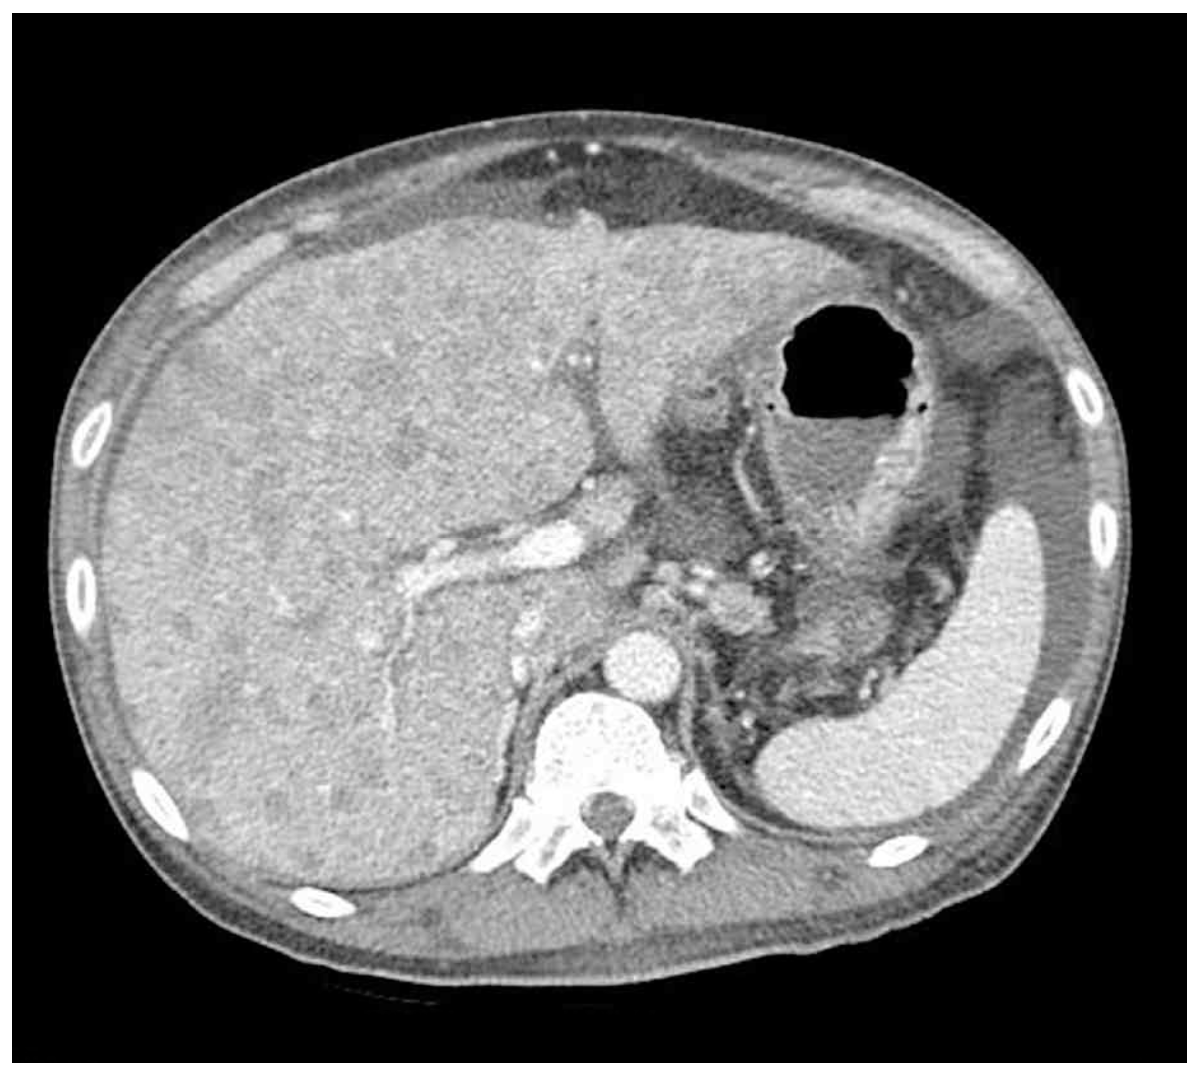

55세 남자가 10일 전부터 배가 아프고 불러진다고 응급실에 왔다. 2개월 전부터 변보기가 힘들고 변도 가늘어졌다고 한다. 혈압 130/85 mmHg, 맥박 105회/분, 호흡 22회/분, 체온 36.5 C이다. 배는 불러있고 압통과 반동압통은 없다. 혈액검사 결과는 다음과 같다. 복부 컴퓨터단층촬영 사진이다. 다음 검사는?

CT: Multifocal hepatic masses, hepatomegaly

• 원인 확인을 위해 시행한 CT에서 간에 다수의 mass가 관찰되는데, 현재 대장암이 의심되는 상황임을 고려할 때 전이성 암의 가능성이 높다. 앞선 Total bilirubin, AST/ALT, CA 19-9 elevation 모두 전이성 간암에서 나타날 수 있는 소견이다.

• 2개월 전부터 배변습관의 변화가 있는 환자에게서 CEA elevation 및 복부 CT상 간에서 다발성 종괴가 확인되므로 대장암 및 대장암의 간 전이가 강력히 의심된다. 따라서, 대장암 진단을 위해 대장내시경을 고려할 수 있다.